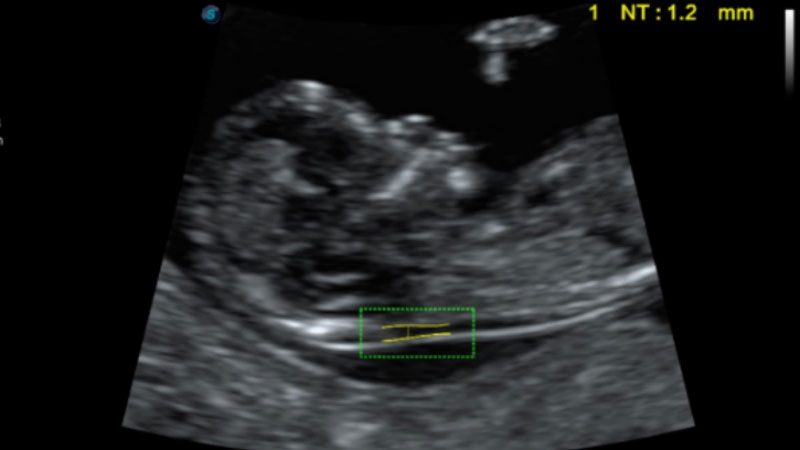

自動(dòng)識(shí)別頸項(xiàng)透明層并獲得NT值,為早孕胎兒畸形篩查提供有效測(cè)量工具,提高診斷效率和診斷信心。